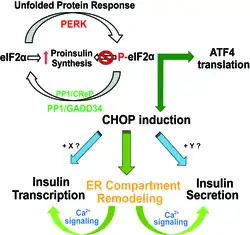

Chop gene deletion has been demonstrated protective against diet induced metabolic syndromes in mice.[60][61] Mice with germline Chop gene knockout have better glycemic control despite unchanged obesity. A plausible explanation for the observed dissociation between obesity and insulin resistance is that CHOP promotes insulin hypersecretion from pancreatic β cells.[62]

Furthermore, Chop depletion by a GLP1-ASO delivery system[63] was shown to have therapeutic effects of insulin reduction and fatty liver correction,[64] in preclinical mouse models.[62]